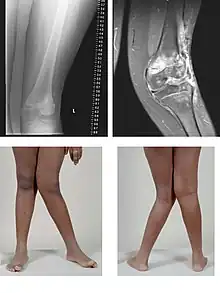

| A very severe case of genu valgum of the left knee following bone cancer treatment | |